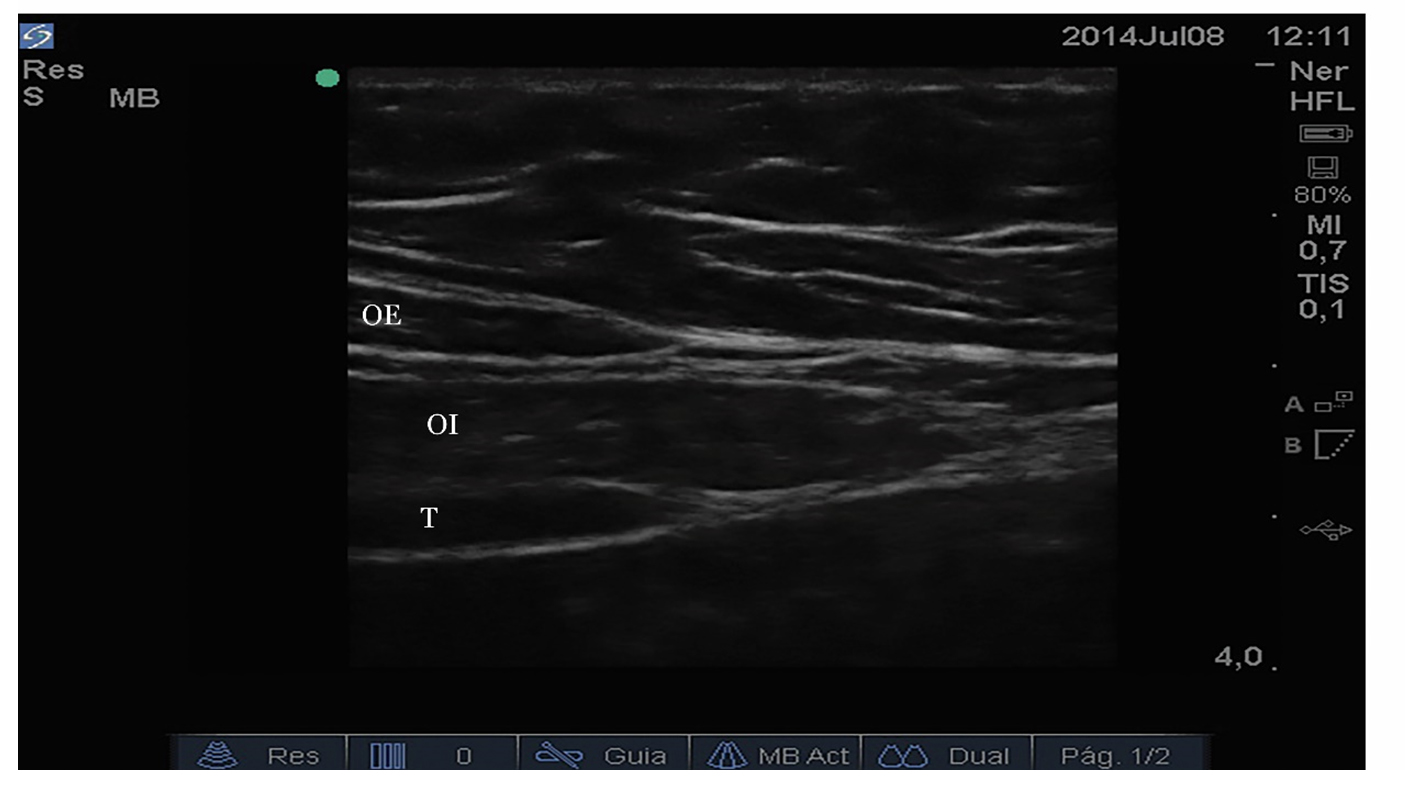

La inervación del músculo recto abdominal, fascia de los rectos, tejido celular subcutáneo y piel en la región umbilical, periumbilical y en la línea media abdominal está dada por los nervios intercostales de T9-T10 y T11 que son divisiones del ramo anterior de la raíz nerviosa de dichos niveles torácicos. Estos nervios transcurren por debajo del reborde costal inferior hasta llegar al plano entre el músculo transverso abdominal y la fascia del oblicuo interno hacia la línea media. En el borde lateral del músculo recto abdominal (línea semilunar), las fascias de los músculos oblicuo externo, oblicuo interno y transverso se unen y medialmente se dividen en la hoja anterior y posterior de la fascia del músculo recto abdominal que, finalmente, se unen en la línea alba (línea media) [6,10].

El paciente debe estar en posición supina con la pared abdominal anterior descubierta. La piel, el transductor y los equipos deben ser preparados de forma estéril. Se debe usar un transductor lineal de alta frecuencia para obtener un corte transversal (alternativamente sagital) del músculo recto abdominal a nivel del ombligo (lateral a este) y mejorar las características para obtener la mejor imagen posible (frecuencia, profundidad, foco y ganancia) (figura 1). Se aconseja utilizar las aplicaciones Doppler para identificar los vasos epigástricos (figura 2) y evitarlos en la trayectoria planeada de la aguja e identificar el peritoneo la grasa peritoneal y las vísceras debajo del peritoneo (movimientos peristálticos) para evitar punciones peritoneales [13,14]. Los nervios intercostales y sus ramas terminales no son fácilmente identificables, por lo que no son el objetivo primario de la infiltración.

Se debe realizar una punción en plano, de medial a lateral (alternativamente céfalo-caudal, cuando se usa el corte sagital), en tiempo real, pasando piel, tejido celular subcutáneo, perforando la hoja anterior de la fascia de los rectos, pasando a través del músculo recto hasta llegar al plano superior a la hoja posterior de la fascia (entre el músculo recto y la hoja posterior de la fascia) [15,16]. Se deben evitar inyecciones intramusculares o peritoneales ubicando exactamente la punta de la aguja en el plano objetivo [16]. Previa aspiración negativa se debe infiltrar anestésico local (frecuentemente de larga acción y asociado a vasoconstrictor para aumentar el tiempo de acción) de forma fraccionada y en tiempo real. Se recomiendan volúmenes de 10 mililitros de anestésico local por lado en adultos y 0,1 mililitros por kilogramo de peso por lado en niños [2,16] (figura 3).